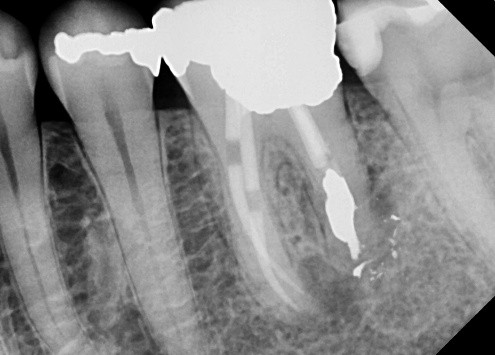

The radiograph shows evidence of

3 / 30

3. (Select ONE OR MORE correct answers)